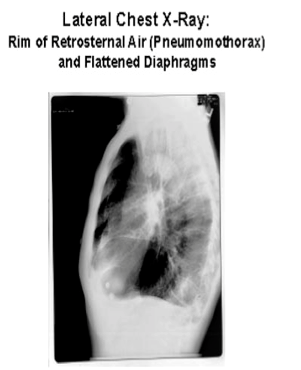

What will you look for on the CXR of someone with emphysema?